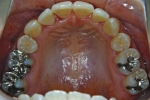

カテゴリー:ClassⅡ division 2 malocclusion (Overbite 5mm以上; 抜歯症例)

しかし、出題基準にも書いてあるように、このケースは欧米の白人によく見られるケースで、東洋人にはきわめて稀である。そこで類似ケースとして過蓋咬合(かがいこうごう)のケースを代替えとして認めるという配慮をしている。過蓋咬合とは非常に強く深く咬んでいる状態を言う。Overbiteとは前歯の垂直的な重なり具合を示す数値で、5mm以上だと上の前歯が下の前歯をほとんど覆い尽くしている感じになるので、前から見ると下の前歯はほとんど見えない状態になる。こういう状態が典型的な過蓋咬合である。典型的なclassⅡ,division 2のケースは過蓋咬合を合併している。

| 治療中